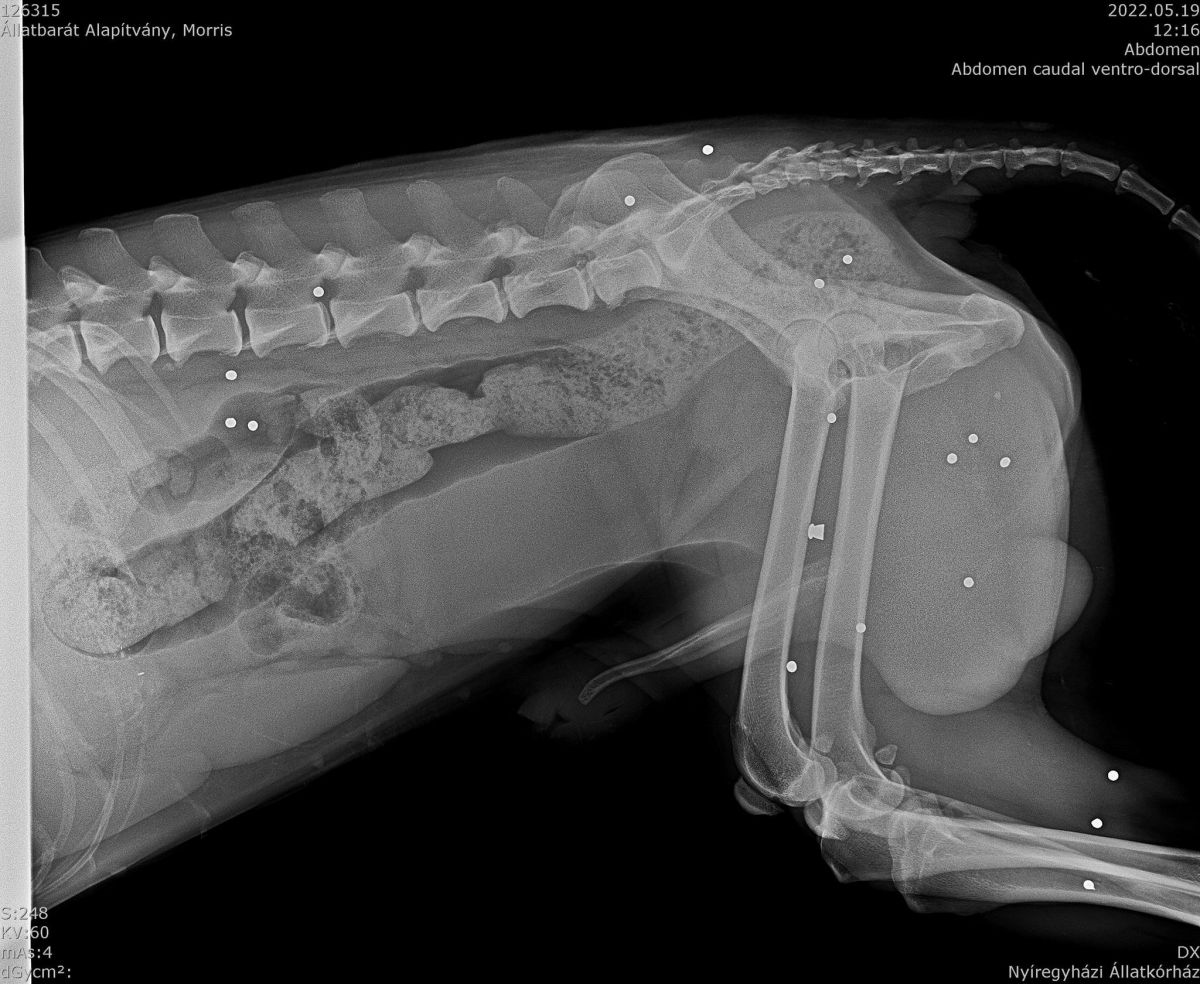

Zudem wurde durch Abtasten festgestellt, dass seine Blase übermäßig gefüllt war. Ausdrücken war nicht möglich und den Katheter einführen auch nicht. Ein dünnerer wurde versucht einzuführen. Dieses klappte mit hängen und würgen. Dann wurden direkt Röntgenbilder gemacht. Und siehe da, auf Morris wurde geschossen. Und vermutlich blockiert eine Kugel, oder Schrot, den Harnweg. Was der arme Kerl ertragen muss, nicht vorzustellen.... Dieses Problem wird nun in Angriff genommen,